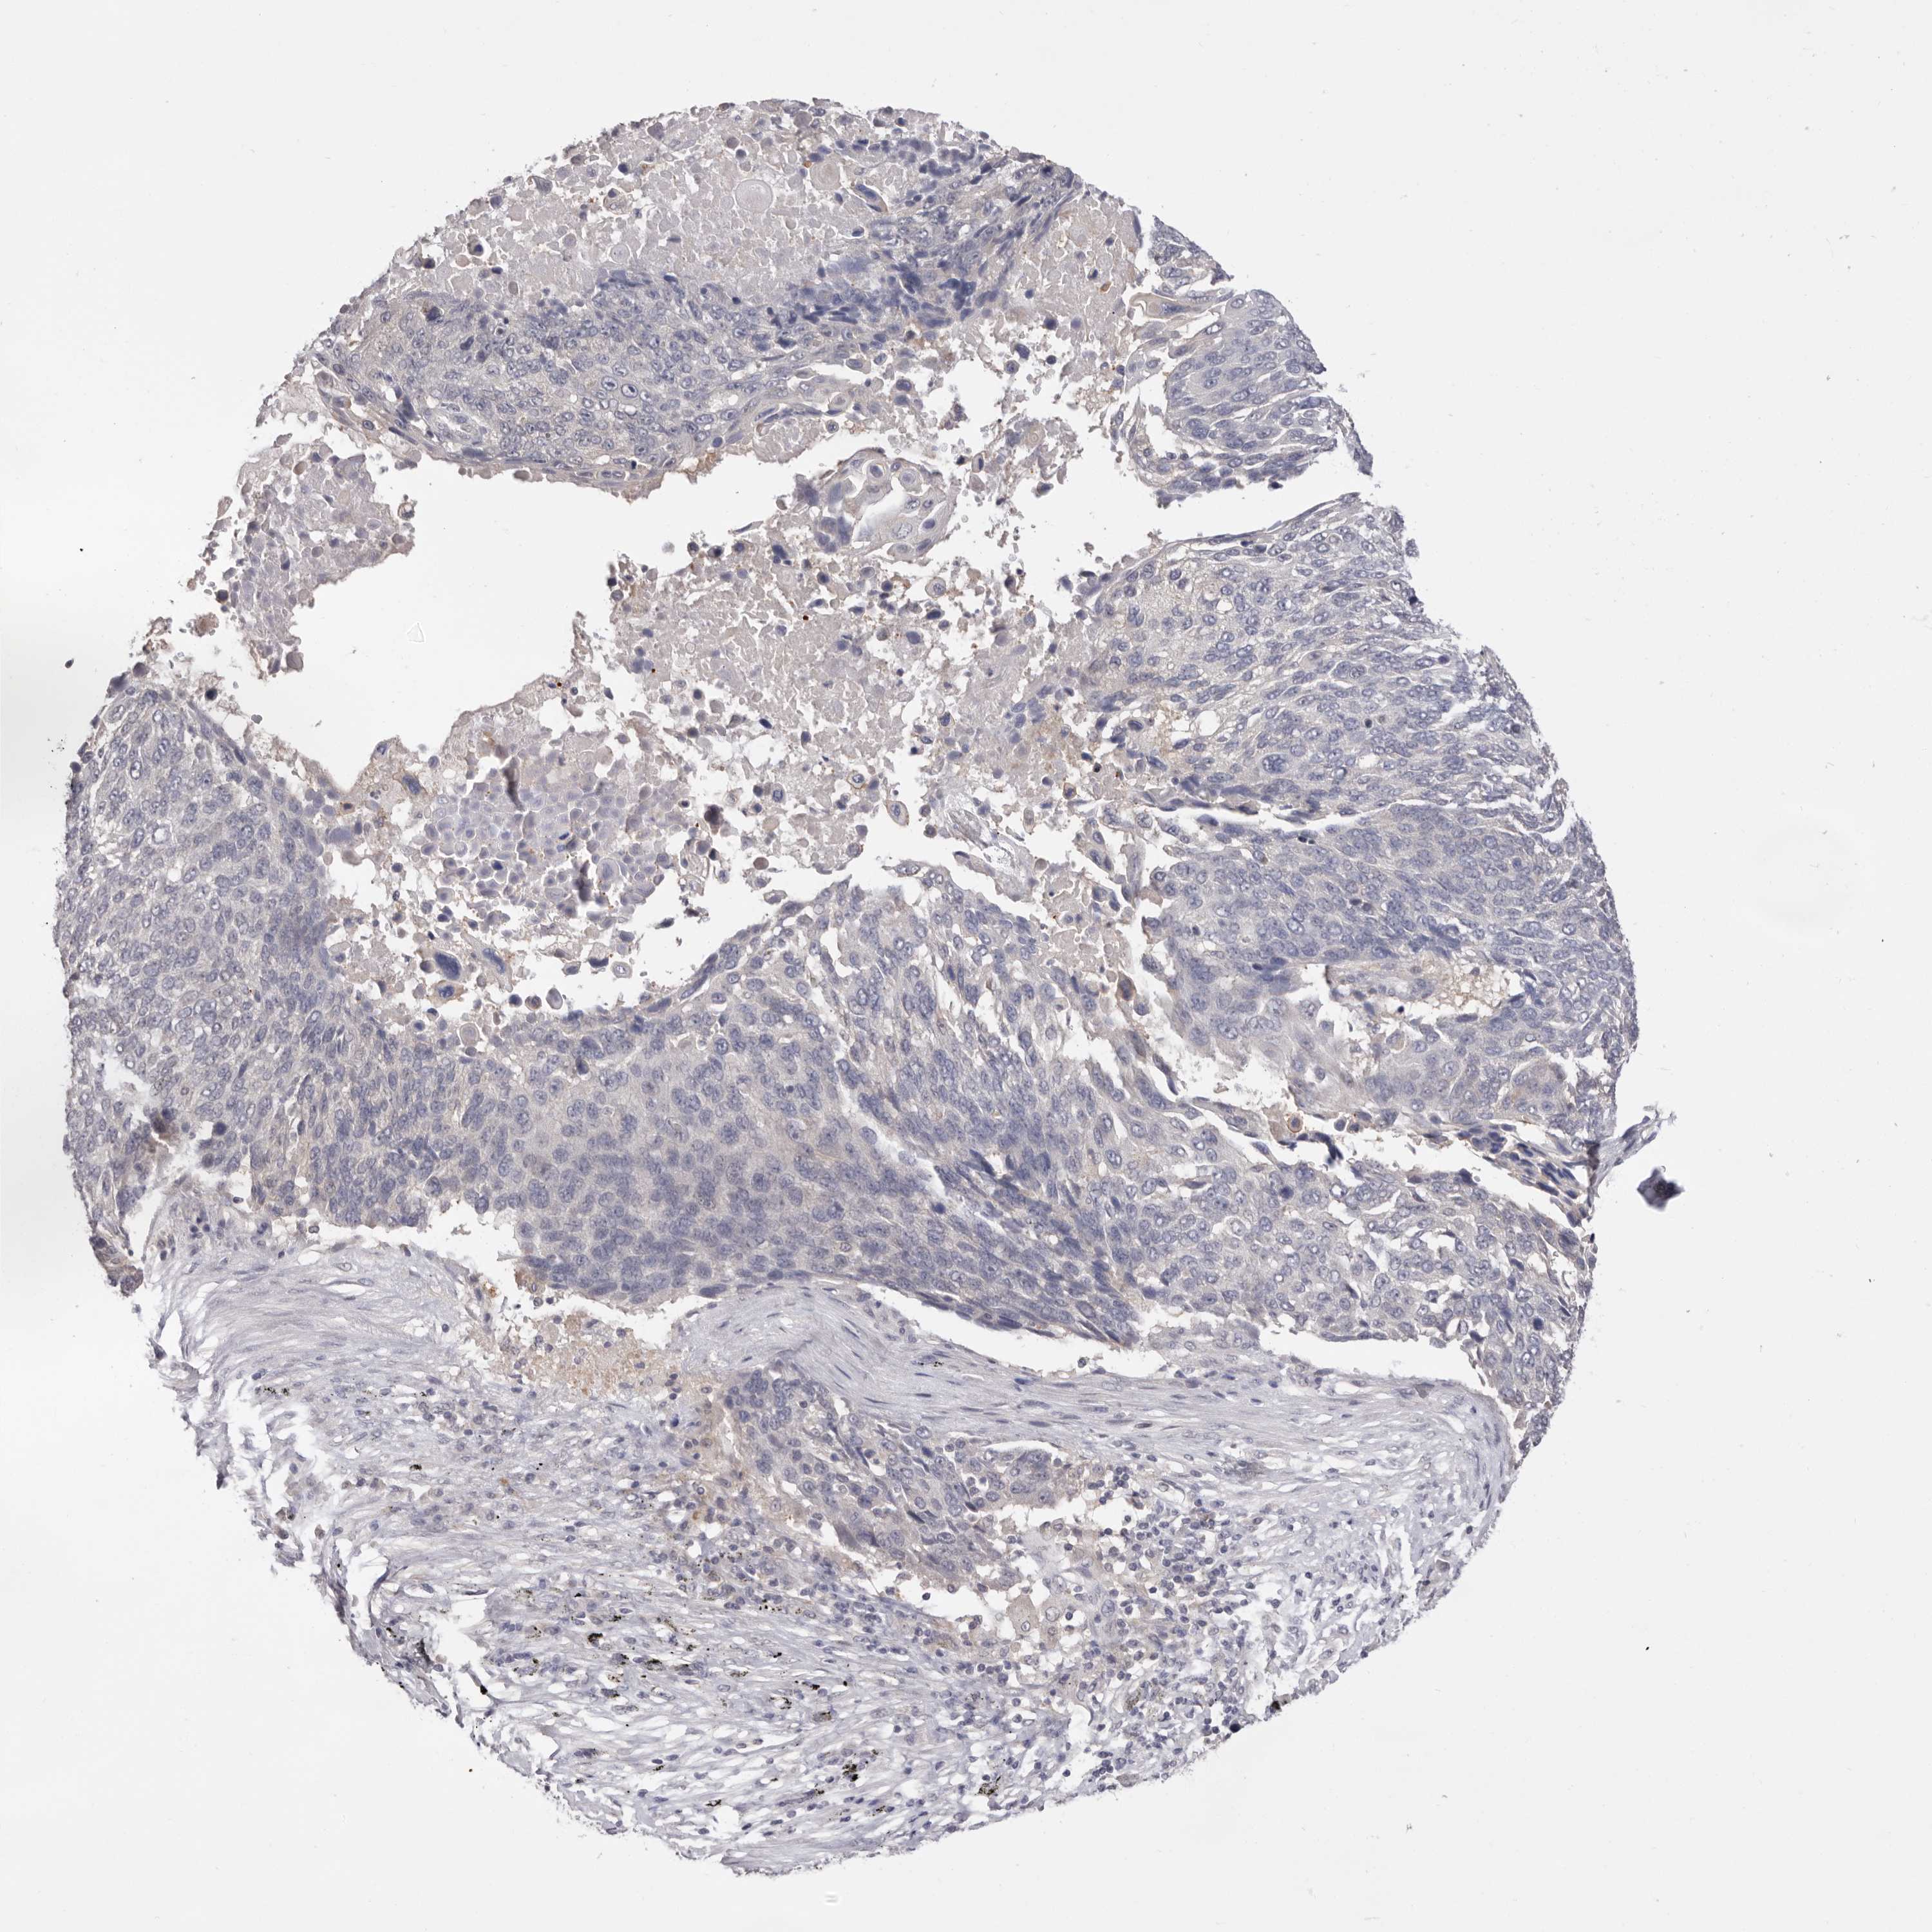

LUNG SQUAMOUS CELL CARCINOMA (TCGA) - Interactive survival scatter ploti

The Survival Scatter plot shows the clinical status (i.e. dead or alive) for all individuals in the patient cohort, based on the same data that underlies the corresponding Kaplan-Meier plots. Patients that are alive at last time for follow-up are shown in blue and patients who have died during the study are shown in red.

The x-axis shows the expression levels (FPKM) of the investigated gene in the tumor tissue at the time of diagnosis. The y-axis shows the follow-up time after diagnosis (years). Both axes are complimented with kernel density curves demonstrating the data density over the axes. The top density plot shows the expression levels (FPKM) distribution among dead (red) and alive patients (blue). The right density plot shows the data density of the survived years of dead patients with high and low expression levels respectively, stratified using the cutoff indicated by the vertical dashed line through the Survival Scatter plot. This cutoff is automatically defined based on the FPKM cutoff that minimizes the p-score. The cutoff can be changed by dragging the vertical line or by entering a cutoff value in the square labeled "Current cut-off".

Under the Survival Scatter plot the p-score landscape (black curve; left axis) is shown together with dead median separation (red curve; right axis). Dead median separation is the difference in median mRNA expression between patients who have died with high and low expression, respectively. It is calculated as follows: median FPKM expression of dead patients with high expression - median FPKM expression of dead patients with low expression. This is intended to aid the user in visually exploring custom cutoffs and the associated p-scores and dead median separation.

Individual patient data is displayed and can be filtered by clicking on one or more of the category buttons on the top of the page. Categories describing expression level and patient information include: high, low, alive, dead, female, male and tumor stages. The scale of the x-axis can be toggled between linear and log-scale by clicking on the "x log" button. Mouse-over function shows TCGA ID, patient information and mRNA expression (FPKM) for each patient.

& Survival analysisi

Kaplan-Meier plots summarize results from analysis of correlation between mRNA expression level and patient survival. Patients were divided based on level of expression into one of the two groups "low" (under cut off) or "high" (over cut off). X-axis shows time for survival (years) and y-axis shows the probability of survival, where 1.0 corresponds to 100 percent.

DOP1A is not prognostic in Lung Squamous Cell Carcinoma (TCGA)

Best expression cut offi

Based on the FPKM value of each gene, patients were classified into two groups and association between prognosis (survival) and gene expression (FPKM) was examined. The best expression cut-off refers the FPKM value that yields maximal difference with regard to survival between the two groups at the lowest log-rank P-value. Best expression cut-off was selected based on survival analysis .

When clicking on this number, the vertical dashed line indicating cut-off, the interactive survival plot, and the Kaplan-Meier curve will be adjusted to show results based on the best expression cut-off.

: 1.32

P scorei

Log-rank P value for Kaplan-Meier plot showing results from analysis of correlation between mRNA expression level and patient survival.

N/A

Average pTPM 2.3

Number of samples 489